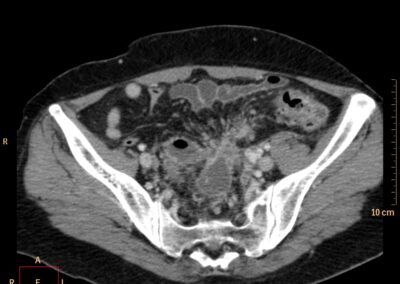

ΕΚΚΟΛΠΩΜΑΤΑ ΠΑΧΕΟΣ ΕΝΤΕΡΟΥ Posted by ΙΠΠΟΚΡΑΤΕΙΟ ΙΩΑΝΝΙΝΩΝ | Dec 16, 2020 | ΠΕΠΤΙΚΟ | 0 ΚΛΙΝΙΚΑ ΣΤΟΙΧΕΙΑ – ΙΣΤΟΡΙΚΟ υποτροπιάζοντες επαναλαμβανόμενοι πυρετοί κυρίως απογευματινές ώρες ΕΡΓΑΣΤΗΡΙΑΚΟΣ ΕΛΕΓΧΟΣ ΑΠΕΙΚΟΝΙΣΤΙΚΟΣ ΕΛΕΓΧΟΣ διακρίνονται τα αποστήματα στην ελάσσονα πύελο, καθώς και εκκολπώματα με εικόνα πάχυνσης του τοιχώματος του σιγμοειδούς ΣΥΖΗΤΗΣΗ